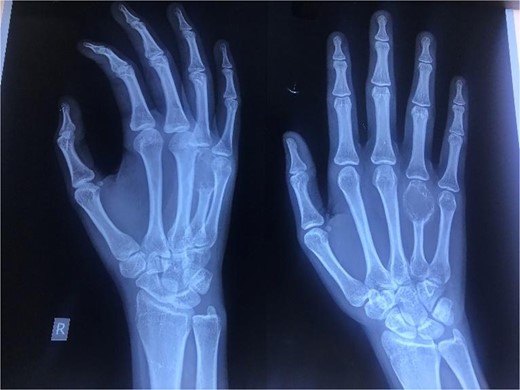

A 20-year-old female, with an unremarkable past medical and surgical history, presented to our clinic with a progressively increasing, painful swelling on the right-hand dorsum on the fourth distal MCP region (Fig. 1). Local examination revealed a 3×3 cm solid immobile swelling at the distal fourth MCP which was painful upon complete extension and flexion. A plain radiograph (Fig. 2 arrow) showed the hallmark expansile soap bubble lesion involving the entire distal fourth MCPJ approaching the articular surface of the MCP. The patient’s routine lab workup was unremarkable. She was counseled regarding all options to make an informed decision and opted for a wide local excision of the lesion along with reconstruction using a free MTPJ transfer.

Preoperative photograph of hands showing swelling in fourth metacarpal of the right hand.

Oblique (left) and antero-posterior (right) view of the right hand revealing an expansile, lytic lesion with a soap bubble appearance over the entire fourth metacarpal bone with thinning of the cortex.